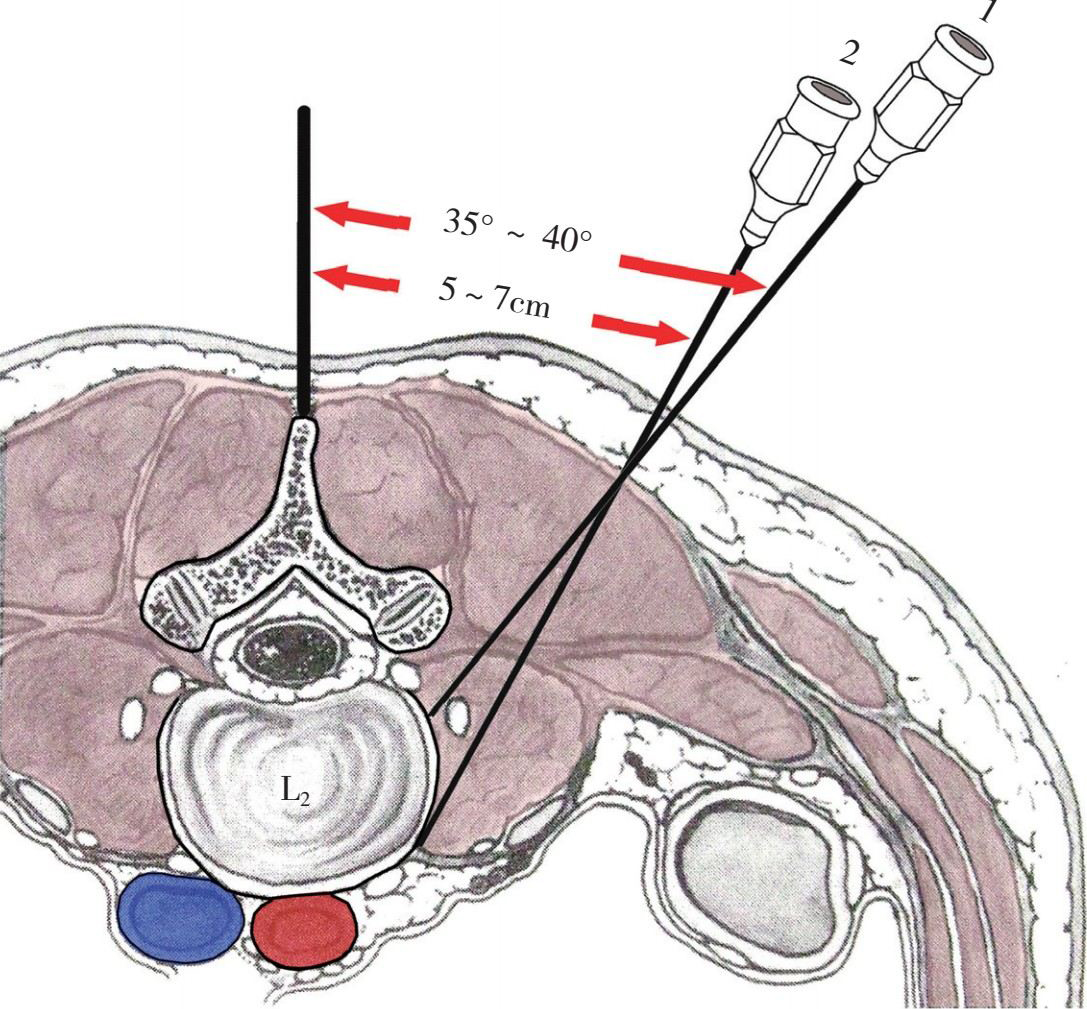

腰段脊神经根出椎间孔后,分成前支和后支,前支在上下两个横突之间向前、向下走行,后支向后绕过关节突至椎板后的肌肉层。夹脊穴封闭即将药液注入横突基部,横突间筋膜的前方,相当于脊神经根出椎间孔的部位,对脊神经前支和后支均起阻滞作用(图4-17、图4-18)。

图4-17 夹脊穴封闭的进针点和穿刺方向

图4-18 穿刺针的针尖一定要到达横突间肌筋膜的前方。在肌筋膜的后方注药效果差

3.具体操作 可采用单针法或三针法,进针点位于棘突旁3~4cm处(图4-19),向前、向内进针,触及第3、4、5腰椎横突下缘的骨组织后,再将针退出少许,改变方向,向下、向内至关节突外侧,于上、下横突之间刺入,穿过横突间韧带至脊神经根出椎间孔的部位(图4-20),开始注入每个间隙10ml的药液,共注3个间隙,双侧症状者可作双侧注药,单侧症状者也可只作单侧注药。

图4-20 进针点旁开棘突中线3.5cm,进针方向向前、向内,触及横突后,将针退出少许,改变方向,内倾角约为20°,向内、向下穿过横突间肌筋膜,针尖到达椎间孔外脊神经根周围注药即可